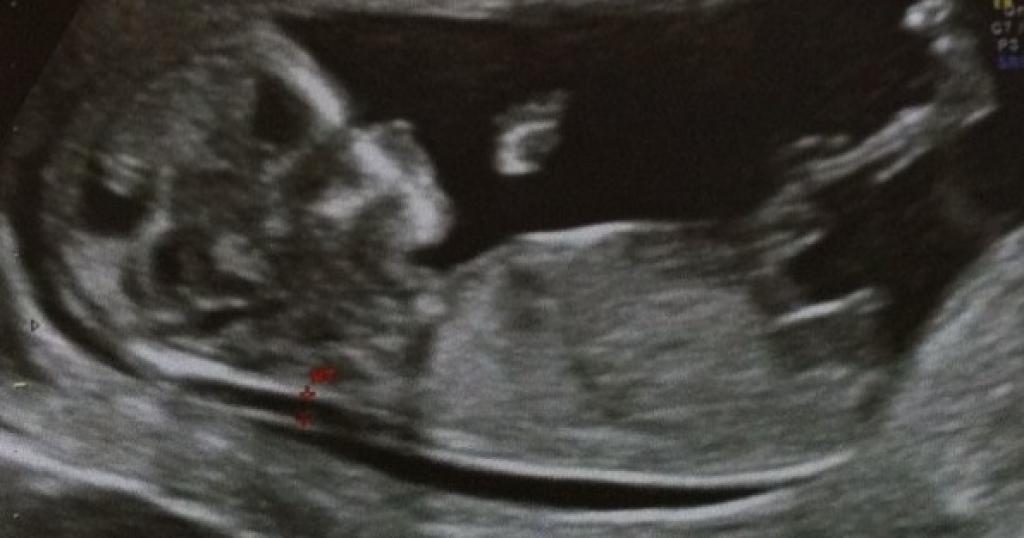

Echographie bebe 12 semaines

Echographie bebe 12 semaines-Echo 16 SA 1 jour le 22/08 bébé mesure 17 cm Tu es une petite fille !! Tableau de biométrie foetale DISTANCE CRANIO CAUDALE (TETE FESSES ) EN MILLIMETRES à 5 semaines d'aménorrhée 1 à 2 mm à 7 semaines d'aménorrhée 8 mm à 9 semaines d'aménorrhée 25 mm à 10 semaines d'aménorrhée 33 mm à 11 semaines d'aménorrhée 43 mm à 12 semaines d'aménorrhée 55 mm à 13 semaines d'aménorrhée 68

Notre bébé a 12 semaines et 3 jours Bonjour, En fait à 12 semaines, il est parfois possible de voir le sexe, mais vraiment pas souvent puisque les organes sont vraiment très petits et pas très matures La plupart des filles de juillet se sont fait dire de ne pas peindre la chambre tout de suite, car la marge d'erreur est assez importante à 12 semainesNous sommes aux anges /font